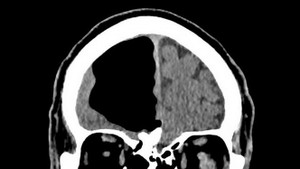

Carlos gần như mất hẳn hơn nửa phần não bộ nhưng vẫn sống khỏe mạnh một cách lạ kỳ.

Cụ ông ở Bắc Ireland không khỏi choáng váng khi hay tin thùy não phải của mình hoàn toàn trống không.